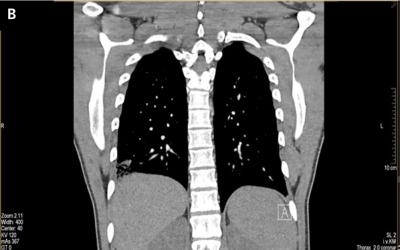

Komplikace nastala v sedmém měsíci při terapii Eliquis tbl. 2× 2,5 mg (snížená dávka po šesti měsících terapie dle SPC): recidiva HŽT ve formě ileofemorální HŽT LDK současně s bilaterální hemodynamicky stabilní plicní embolizací (provedeno CTAG) (obr. 2). Laboratorně hodnota D-dimerů 885 µg/l [1..190], hodnota FVIII 174 IU/ml [norma do 150], provedený základní onkologický screening byl v normě, byly vyloučeny „vzácné“ formy trombofilie (F:VII, IX, XI, XII, JAK-2 neg.).